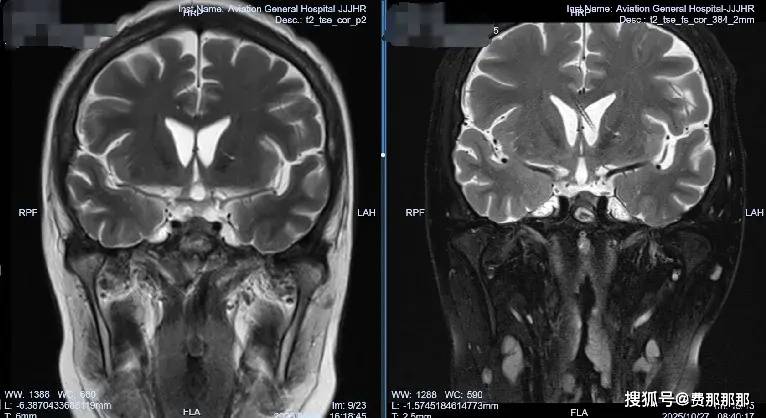

肖庆主任决定采取分阶段治疗策略:首先在2025年8月13日进行“腰大池置管引流”,建立初步引流通道;随后在8月21日实施“脑室腹壁外引流术”,建立持续引流通道。“精准的脑脊液管理是真菌性颅内感染治疗的关键。”肖主任强调,“我们不仅要控制感染,更要通过精细的引流调节,维持正常的颅内环境,为大脑恢复创造最佳条件。”

当引流管夹闭一周后,李女士没有出现任何不适,医疗团队知道,他们的治疗策略奏效了。2025年10月28日,肖庆主任为李女士成功结扎了引流管。那一刻,病房里洋溢着久违的轻松气氛。

肖庆主任表示,这个病例的成功得益于“个体化的脑脊液管理策略”与“精准的抗真菌治疗”的完美结合。“真菌性颅内感染治疗的最大挑战在于,它容易导致脑室系统粘连,进而形成脑积水。而通过精准的脑脊液外引流管理,我们不仅控制了颅内压力,还直接改善了药物分布,防止了并发症的发生。”

如今,李女士已重返正常生活。医生叮嘱她一个月后复查脑脊液、三个月后复查头颅影像学检查。“我知道康复之路还很长,但至少现在我看到了希望。”出院时,李女士说道。